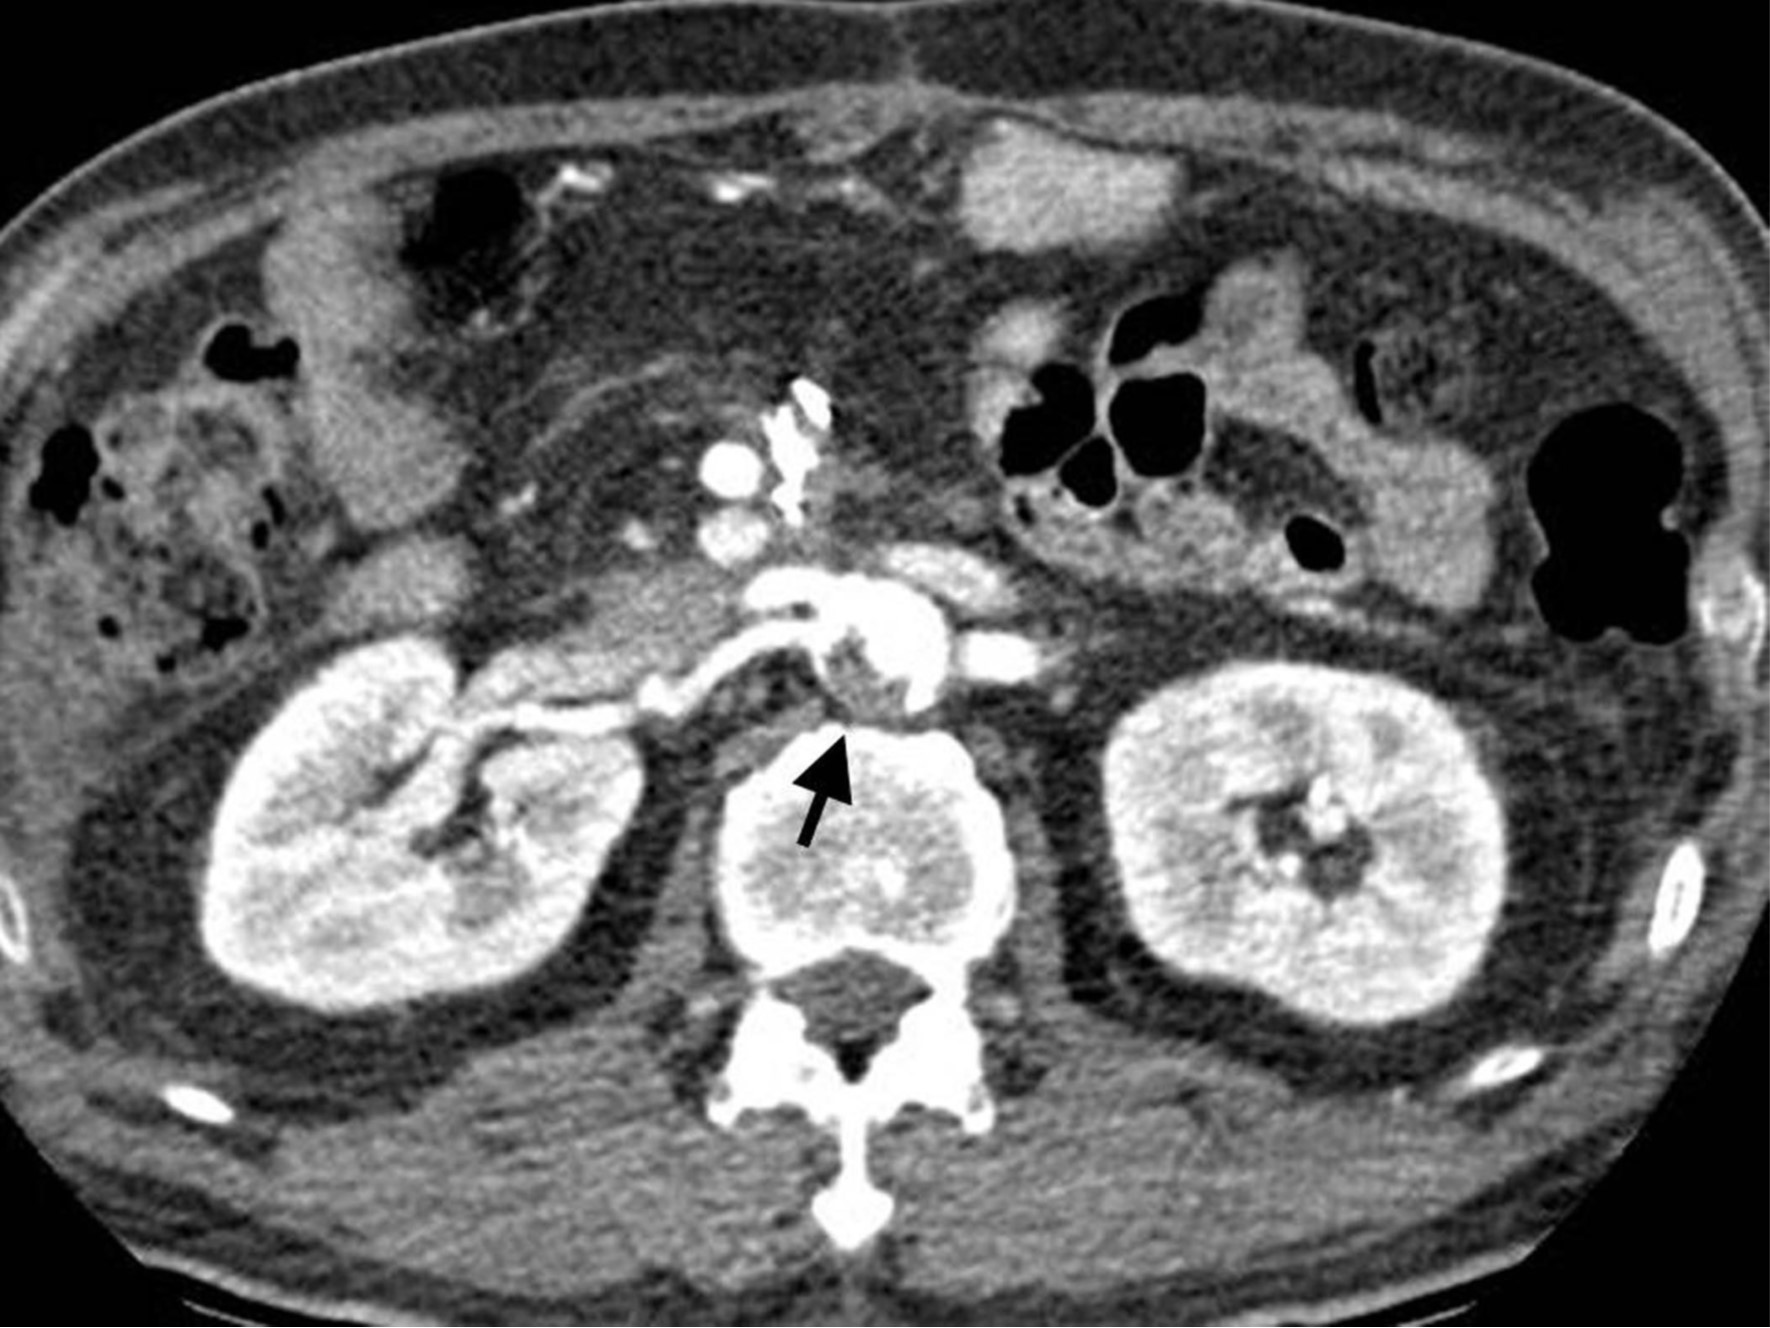

복부 CT에서, 복부대동맥의 신장동맥 분지부에 혈전이 관찰되었음(Fig. 1). CTA에서 좌측 오금동맥에서 후정강동맥의 종아리동맥 분지부까지 긴 분절에 걸쳐 폐쇄가 있었음(Fig. 2).

Fig. 1.

Fig. 1. CT Angiography shows large filling defect in renal artery branching level of the abdominal aorta (arrow).